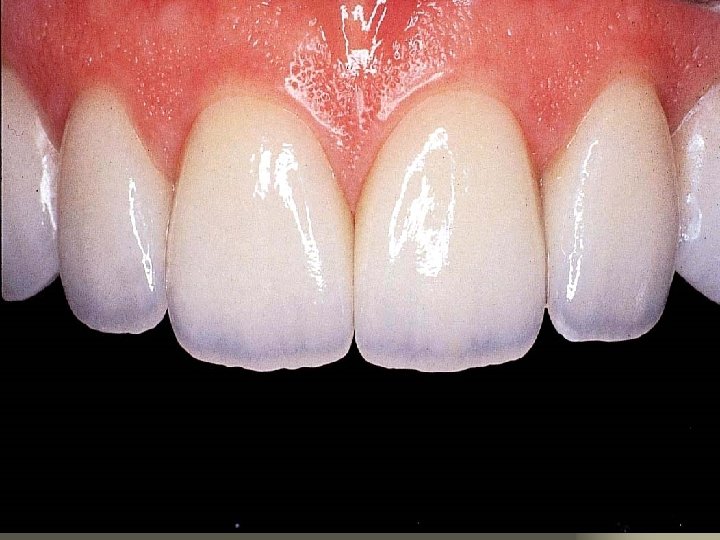

All Ceramic Crown Preparation Design & Function Shoulder marginal integrity structural durability periodontal preservation resistance

All Ceramic Crown Preparation Design & Function Shoulder marginal integrity structural durability periodontal preservation resistance Axial Reduction retention and resistance structural durability

All Ceramic Crown Preparation Design & Function Shoulder marginal integrity structural durability periodontal preservation resistance Axial Reduction retention and resistance structural durability Rounded Line Angles structural durability

All Ceramic Crown Preparation Design & Function Shoulder marginal integrity structural durability periodontal preservation resistance Concave Cingulum Reduction Axial Reduction structural durability retention and resistance structural durability Rounded Line Angles structural durability

All Ceramic Crown Preparation Design & Function Shoulder marginal integrity structural durability periodontal preservation resistance Vertical Lingual Wall retention and resistance Concave Cingulum Reduction Axial Reduction structural durability retention and resistance structural durability Rounded Line Angles structural durability